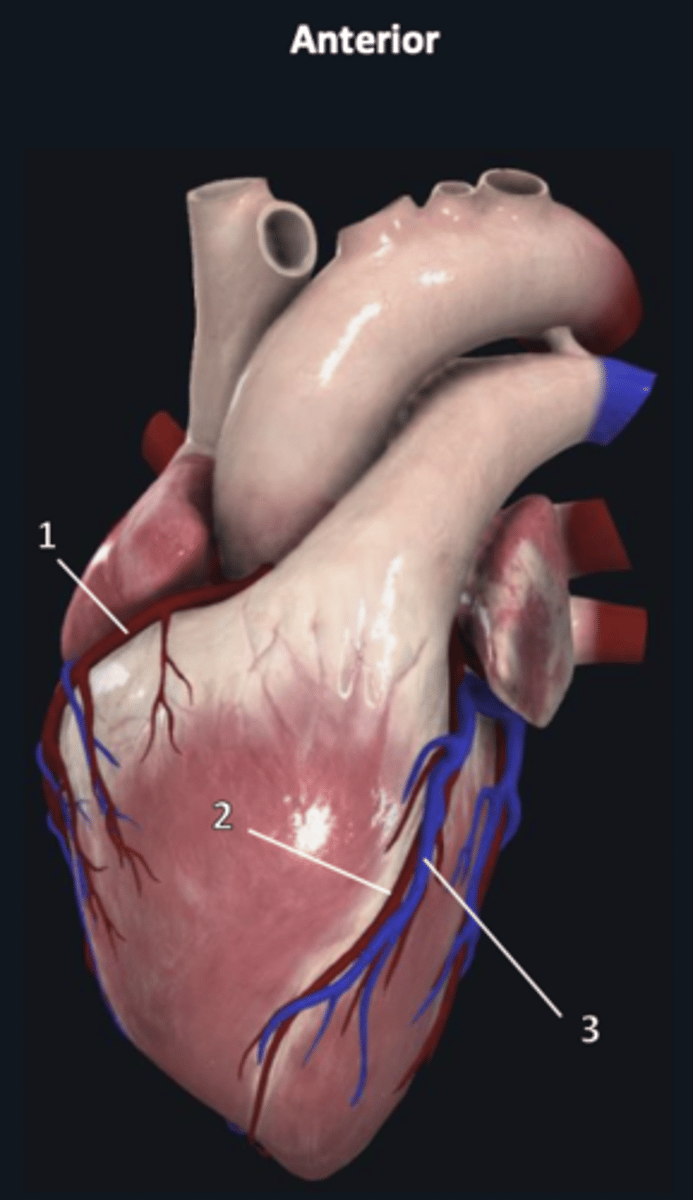

right coronary artery

1

anterior interventricular artery

2 (red)

great cardiac vein

3 (blue)

anterior interventricular artery

2 (red)

great cardiac vein

3 (blue)